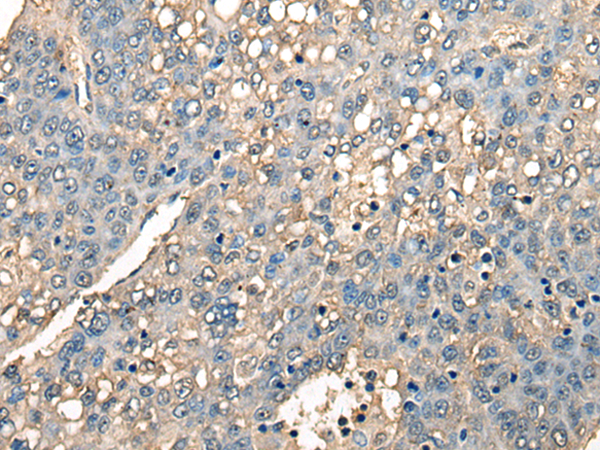

IHC positive control: |

Human liver cancer and human esophagus cancer |